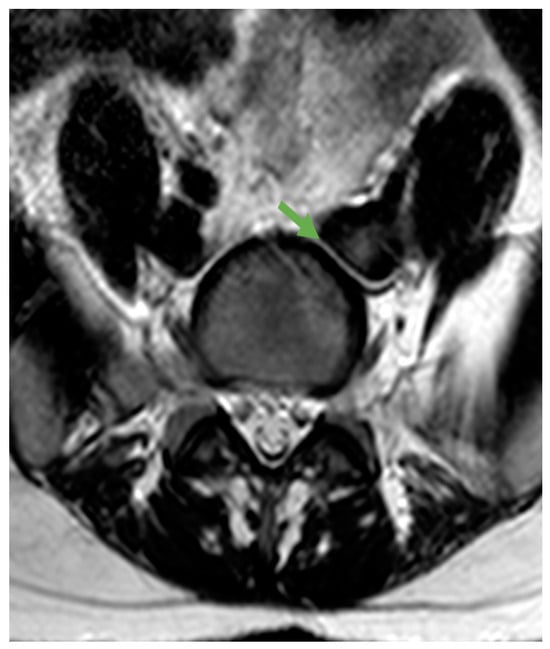

For proper preoperative planning, magnetic resonance imaging (MRI) is essential to identify different structures and to qualify the approach difficulty. First, the surgeon must determine the location of the aortoiliac bifurcation. The approach is classified as type 1 when performed caudally to the bifurcation and as type 2 when performed laterally to the bifurcation (usually on the left side). To approach the L5-S1 disc, a type 1 approach is usually used, whereas to access L4-L5 discs, a type 2 approach is commonly required. The type 1 approach is further classified as “narrow window” when the gap between the common iliac veins is 1.5–3 cm (Figure 1a); if this distance is >3 cm, the case is classified as “wide window” (Figure 1b).

Figure 1. L5-S1 approach. (a) Type 1 “narrow”; (b) Type 1 “wide”; (c) When the distance between the right and left iliac vessels is <1.5 cm, a type 2 approach (through the oblique corridor) is used. Vascular structures are shown outlined in red. The green arrows indicate the space available for approach.